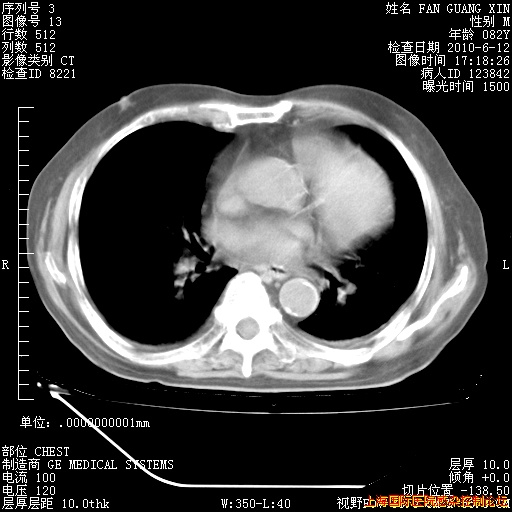

6月12日纵膈窗

整整相隔30天的肺部CT好像有所好转啊。甲强龙减量第3天,需要观察体温。

海管,自昨日你和我通完话后,不知您岳父消化道症状有无缓解?体温怎样?阅读7.12日胸部ct,个人认为目前激素治疗是有效的,甲强龙减量是适宜的。因在抗痨治疗,需密切观察肝功、肾功能和血常规。不过,老年、长期住院和大量使用激素,很担心菌群失调发生